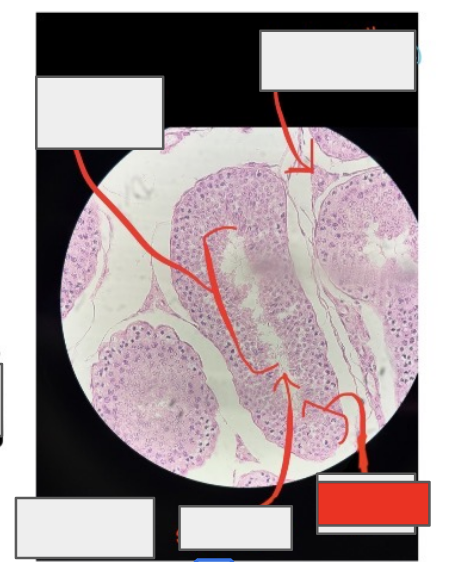

ovary

what organ is this from?

Primordial follicle

What is this whole thing?

Primary oocyte

Follicular cells

(the things that surround it)

Primary follicle

Granulosa cells